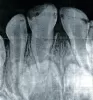

Добрый день. Мой ребенок, 2 года, сломала зуб. В поликлинике нам рекомендовали сделать фторирование (но у них нет препарата, они не могут), в другой платной рекомендовали не трогать зуб, если не беспокоит, а если будет болеть — лечить под ингаляционным наркозом «Севоран». Не хочется ребенка под наркоз. Что посоветуете?

Здраствуйте! Подскажите пожалуйста, у моего 2-летнего ребенка кариес на передних зубках, что лучше: серебрение или глубокое фторирование? Спасибо!